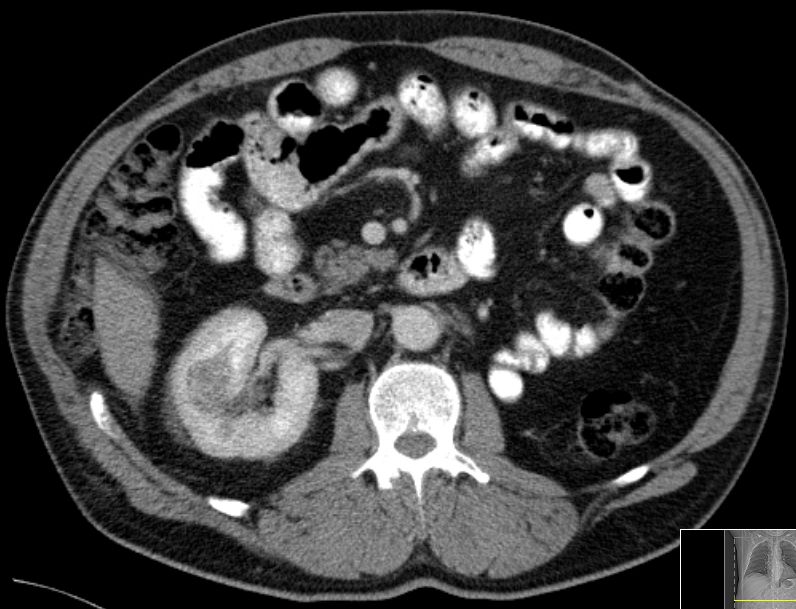

61-jähriger Mann mit einem Nierenzellkarzinom

links mit Lungenmetastasen vor 7 Jahren. Therapie mit Sunitinib, dann Pazotinib,

dann Axitinib, dann Sorafenib. Jetzt Metastase in der kontralateralen Niere.